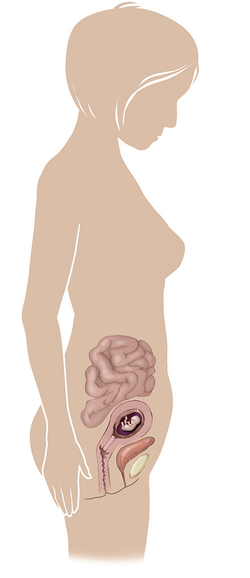

مراحل تطور الجنين أثناء الحمل

تطور الجنين خلال فترة الحمل على ثلاثة مراحل: أول 14 أسبوع من الحمل ، ثم تطوره بداية من الأسبوع 14 وحتى 28 أسبوعا ، ثم الثلث الأخير من 28 إلى 40 أسبوع من الحمل ... المزيد

مراحل تطور الحمل أسبوعيا بالصور

مراحل تطور الحمل أسبوعيا لكل من الأم والجنين داخل الرحم مدعومة بالصور التوضيحية ... المزيد